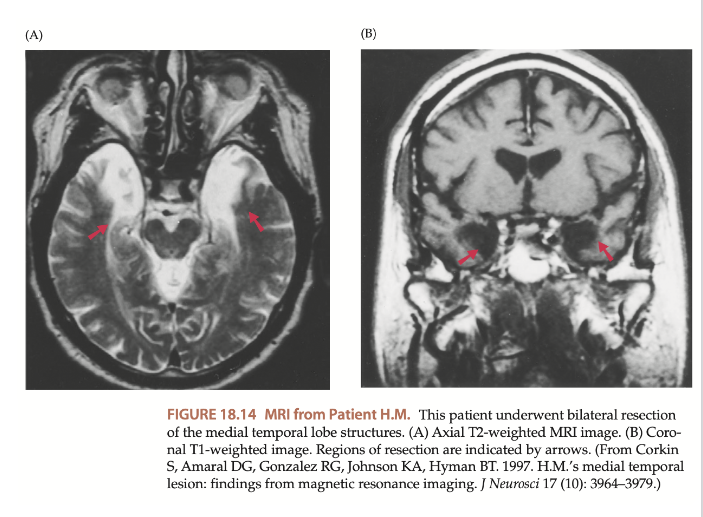

verschillende geheugensystemen: casus H.M.

= Henry Molaison

leed aan ernstige epilepsie

experimentele operatie: deel van hersenen verwijderd

verwijderen van beide mediale temporale kwabben → incl. hippocampus

doel: aanvallen stoppen, MAAR: onverwachte gevolgen

casus H.M. → effecten van de operatie

geen vorming van nieuwe langetermijnherinneringen

werkgeheugen (kortetermijngeheugen) bleef intact → maar slechts 20-30 seconden

herinneringen van vóór operatie bleven behouden, maar recente gebeurtenissen niet meer herinneren

algemene intelligentie bleef onaangetast (IQ-score van 112)

nog steeds mogelijks om nieuwe motorische vaardigheden te leren (impliciet geheugen), maar kon zich daar niets van herinneren (expliciet geheugen)